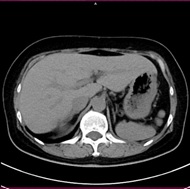

胸部CT画像 腹部CT画像